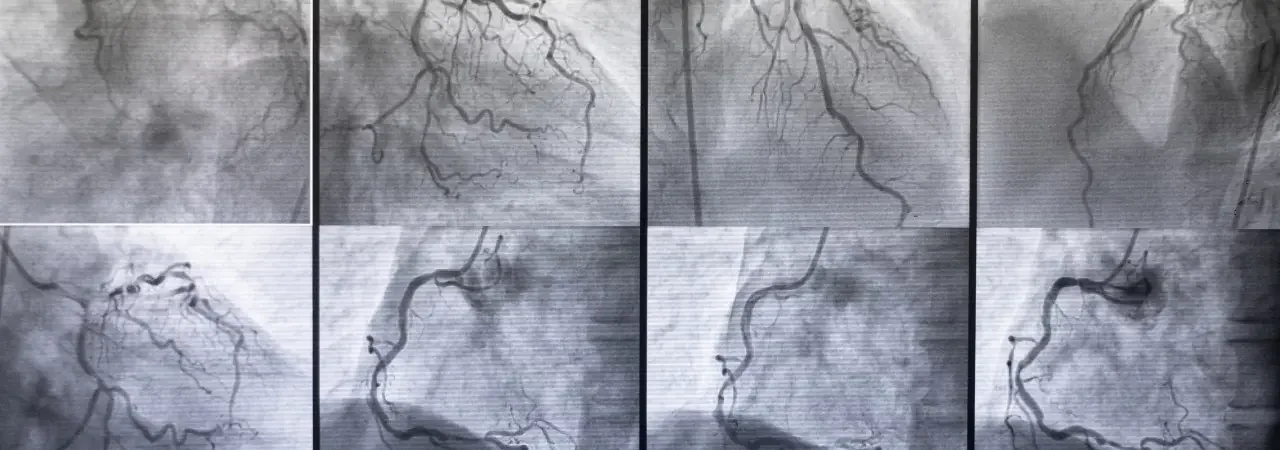

Anjiyografi | Kalp Damar Tıkanıklıklarının Tanısında Altın Standart

Anjiyografi ve koroner anjiyografinin tanıdaki rolünü, işlem öncesi hazırlığı, adım adım süreci, olası riskleri ve tıkanıklık saptand�...